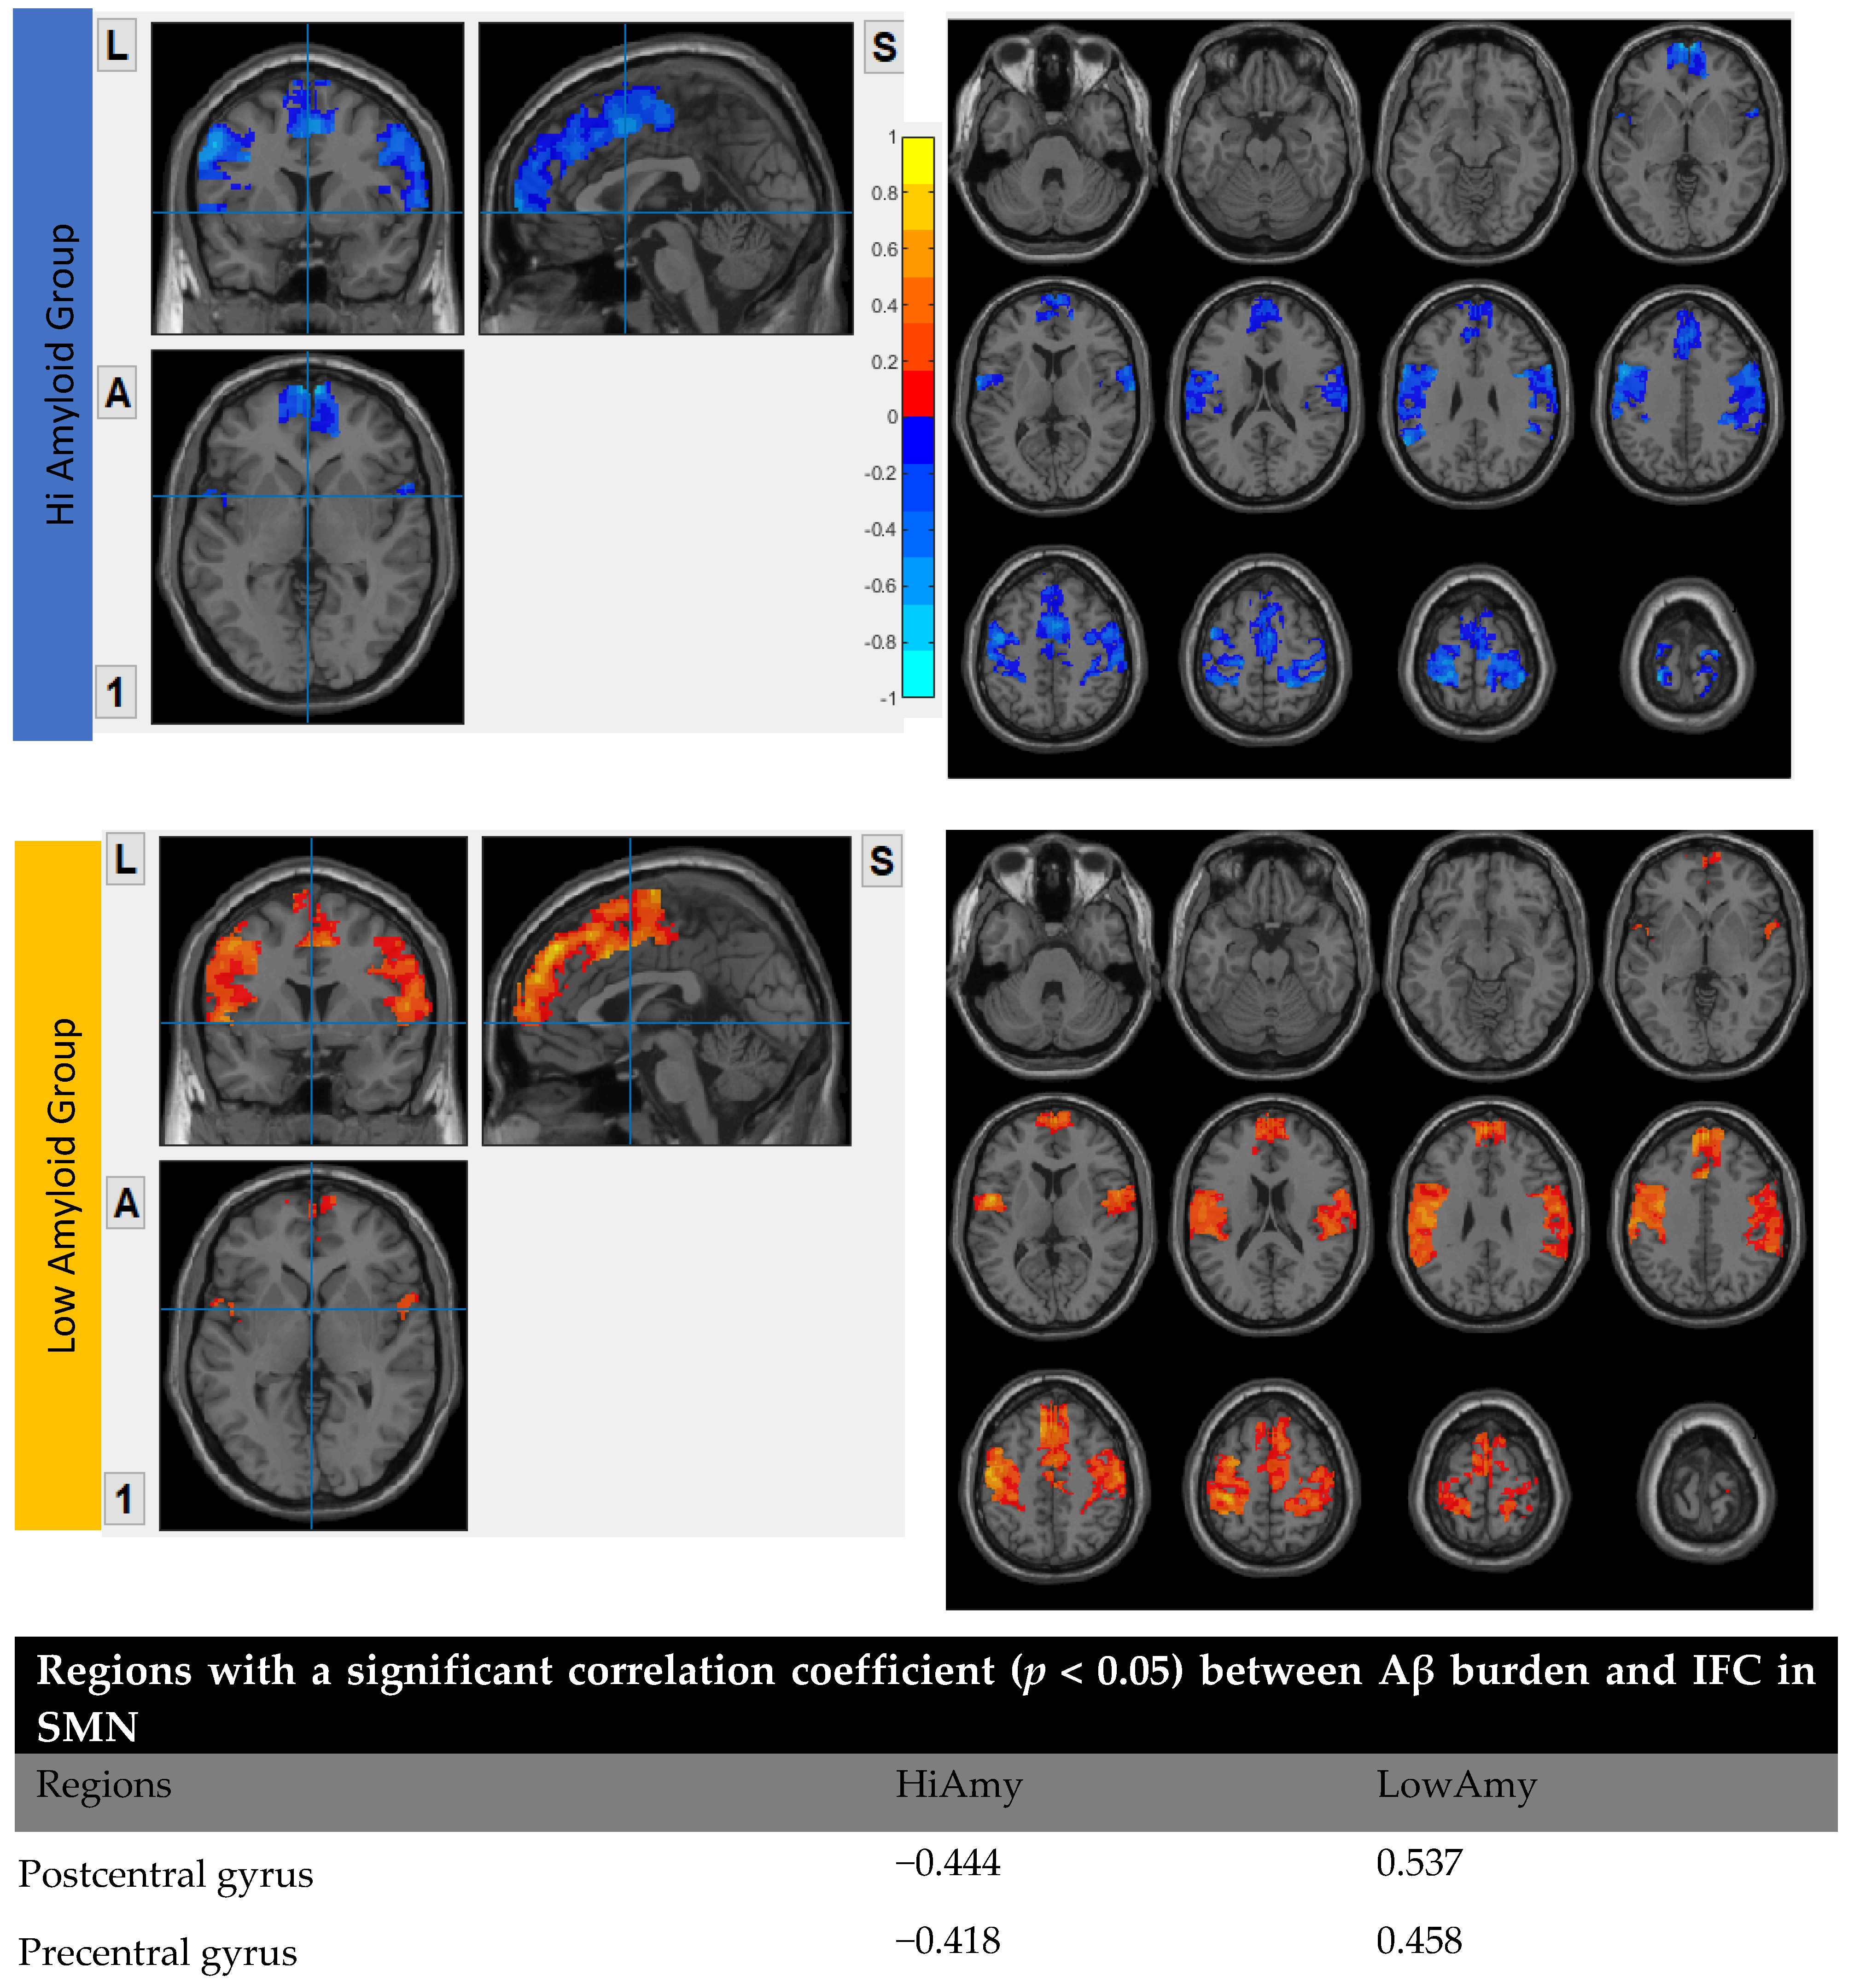

7.5. Within SMN